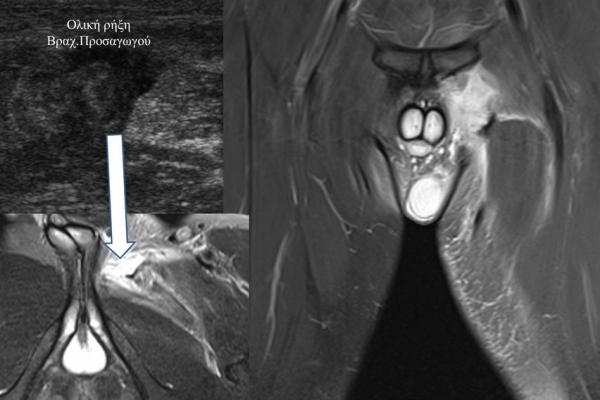

- Παθήσεις Ώμου (πχ ρήξη στροφικού πετάλου)